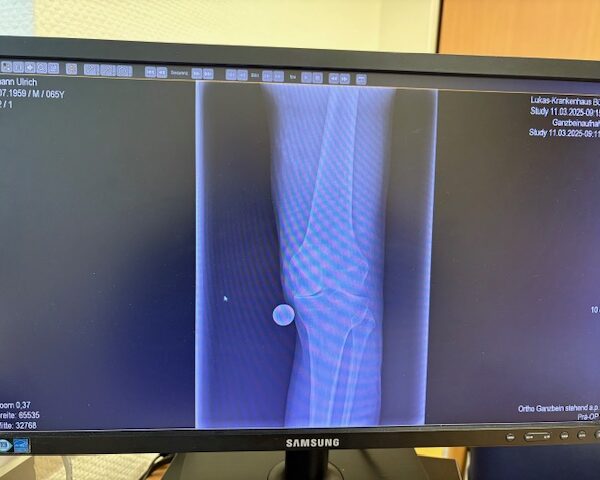

Ο ακτινολογικός έλεγχος (ακτινογραφίες/μαγνητική τομογραφία) ανέδειξε προχωρημένη οστεοαρθρίτιδα του έσω κονδύλου, με πλήρη διατήρηση του έξω διαμερίσματος και της επιγονατιδομηριαίας άρθρωσης. Με βάση αυτά τα ευρήματα, ο ασθενής ήταν ιδανικός υποψήφιος για μερική (μονοκονδυλική) αρθροπλαστική γόνατος.

Πραγματοποιήθηκε απεικόνιση και ψηφιακός σχεδιασμός της επέμβασης, ώστε να προσδιοριστεί με ακρίβεια το μέγεθος και η θέση των προθέσεων. Ο στόχος ήταν να αποκατασταθεί η φυσιολογική μηχανική του γόνατος, διατηρώντας ανέπαφα τα υγιή τμήματα της άρθρωσης, τους συνδέσμους και τους γύρω μυς.

Στον ασθενή τα εμφυτεύματα που χρησιμοποιήθηκαν είναι της εταιρείας Zimmer-Biomet Persona Μηριαίο μέγεθος 6, κνημιαίο μέγεθος Η και ενθέμα (inlay) Η li. 8mm.